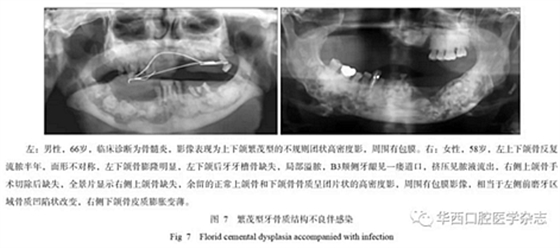

牙骨質(zhì)結(jié)構(gòu)不良具有多樣性的影像學(xué)特征,所以在臨床上也表現(xiàn)為不同的癥狀,由于該疾病生長比較緩慢,患者在未出現(xiàn)癥狀前經(jīng)常不會來就診。當(dāng)患者出現(xiàn)癥狀時或者醫(yī)生偶然在拍攝片子后發(fā)現(xiàn)根尖暗影,就會遇到診斷的問題,最常造成診斷不清的是診斷為慢性根尖周炎,按照慣性思維往往首先思考根尖周炎,就采用傳統(tǒng)的根管治療方式進(jìn)行治療,但治療以后發(fā)現(xiàn)根尖的骨質(zhì)改變更加明顯,極端的甚至出現(xiàn)長時間的癥狀不消失或者不愈,或者形成骨髓炎改變。多發(fā)性或者泛發(fā)性的牙骨質(zhì)結(jié)構(gòu)不良常常造成牙脫落或者拔牙后出現(xiàn)感染,進(jìn)而出現(xiàn)骨髓炎改變,頜骨骨皮質(zhì)密度增高、增厚,為炎性反應(yīng)性增生所致(圖7)。

發(fā)生于后牙的牙骨質(zhì)結(jié)構(gòu)不良常常表現(xiàn)為頜骨膨脹,臨床容易診斷為腫瘤,牙骨質(zhì)結(jié)構(gòu)不良以往被稱為“假性牙骨質(zhì)瘤”就可以表明這類腫瘤的特性,并且往往造成誤診,而病理由于組織切取和牙、骨等硬組織的原因,常常診斷也比較困難,需要結(jié)合X線檢查來確定[1]。對于泛發(fā)性的牙骨質(zhì)結(jié)構(gòu)不良,X線的診斷應(yīng)該更具有優(yōu)勢,尤其是全景片可以清楚地顯示上下頜骨的病變,對于影像的相似性判斷更加容易,而CBCT的優(yōu)勢在于可以清楚了解病變區(qū)內(nèi)的結(jié)構(gòu)、密度、邊界及相鄰牙等結(jié)構(gòu)受影響的變化情況。